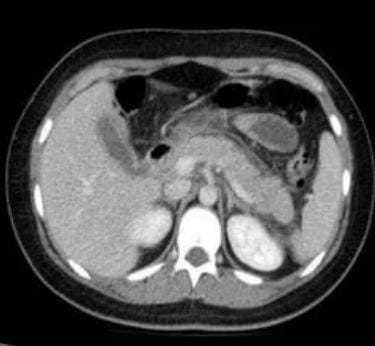

A CT scan of the abdomen showed a bulky pancreas with moderate peripancreatic fluid suggestive of Acute Pancreatitis. The patient was treated with intravenous fluid, analgesics, and antiemetics. His serum amylase and lipase levels became normal after 3 days. Two days later, he was discharged home with a complete resolution of his symptoms.

Fig 1- CT abdomen showing Acute Pancreatitis with Peripancreatic fluid with no evidence of necrosis